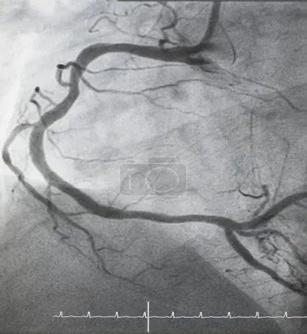

冠脉造影:诊断冠心病的“金标准”

冠脉造影是诊断冠心病的“金标准”,更为精确,适用于高度怀疑冠心病的人群(有典型的缺血性心绞痛症状、有胸痛但症状不典型、心电图或影像检查阳性等)。

所以,做心电图是看电路通不通,有没有短路漏电及异常的电路。做心脏超声就是看犹如四居室房子的心脏各房间情况,比如房间有几个、有多大、墙上是否有漏洞、墙壁有多厚、房门开关弹性是否好,关门时是否严实和漏风;冠脉造影是看水管是否有堵塞、有没有生锈、需不需要疏通。因此三种检查用途各异且互相补充,不能替代。体检中,我们会根据您的情况做项目建议。